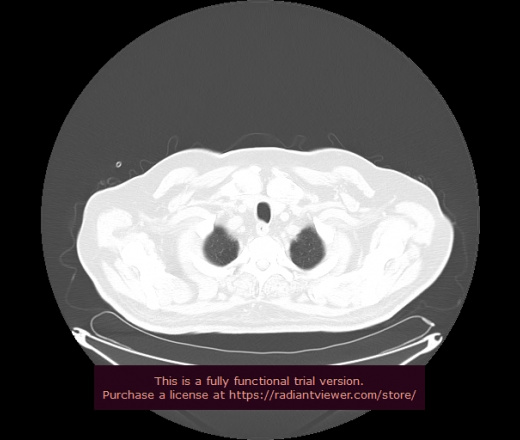

Уважаемые коллеги, если имеется интерес, сможете ли Вы спрогнозировать дальнейшее +-одинаковое течение процесса у 4 данных разных пациентов? Зацепиться где-то можно очень просто, где-то нельзя.